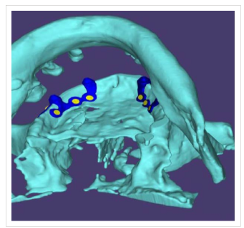

- CBCT-based 3D reconstruction

- CAD-based virtual implant design

- Passive adaptation of custom subperiosteal implant framework

- Fixation using titanium screws (multiple anchorage points)